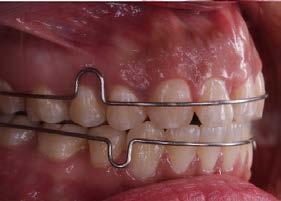

En su análisis facial la paciente presentó un perfil convexo con un tercio inferior aumentado, patrón dolicocefálico severo de VERT, sonrisa gingival e incompetencia labial (Figura 1 A). Durante la exploración intraoral encontramos mordida abierta anterior con apiñamiento severo superior (-13mm) e inferior (-11.5mm), líneas medias desviadas y no coincidentes con la línea media facial, el diente 11

mutilado y con tratamiento de conducto inconcluso, overbite -3mm y overjet 8mm (Figura 1 B).

En la fase de alineación se utilizó una secuencia de arcos comenzando con el arco 0.012” NiTi, 0.014” NiTi y 0.016” Niti. Se realizó la tracción del diente 21 y se mantuvo en boca hasta comenzar la fase de trabajo, posteriormente se realizó la extracción (Figura 3).

Durante la fase de trabajo se realizaron sets de intrusión y utilización de close coil; una vez cerrado el espacio entre los incisivos laterales, se indicó el uso de elásticos de clase III 3/16 4.5 oz para corregir la mordida borde a borde (Figura 4).